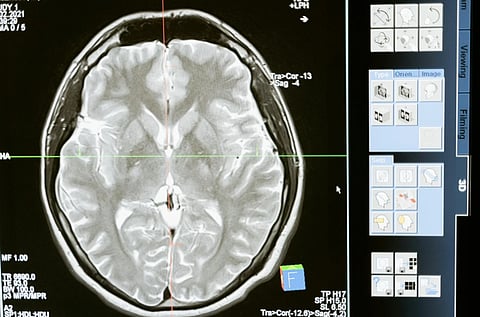

Image of MRI scan of a human brain displayed on a computer screen, showing cross-sectional details in shades of gray. Interface panels with icons on the right.

Traditionally, Parkinson's researchers have focused on protein accumulation and neuronal lossPhoto by MART PRODUCTION